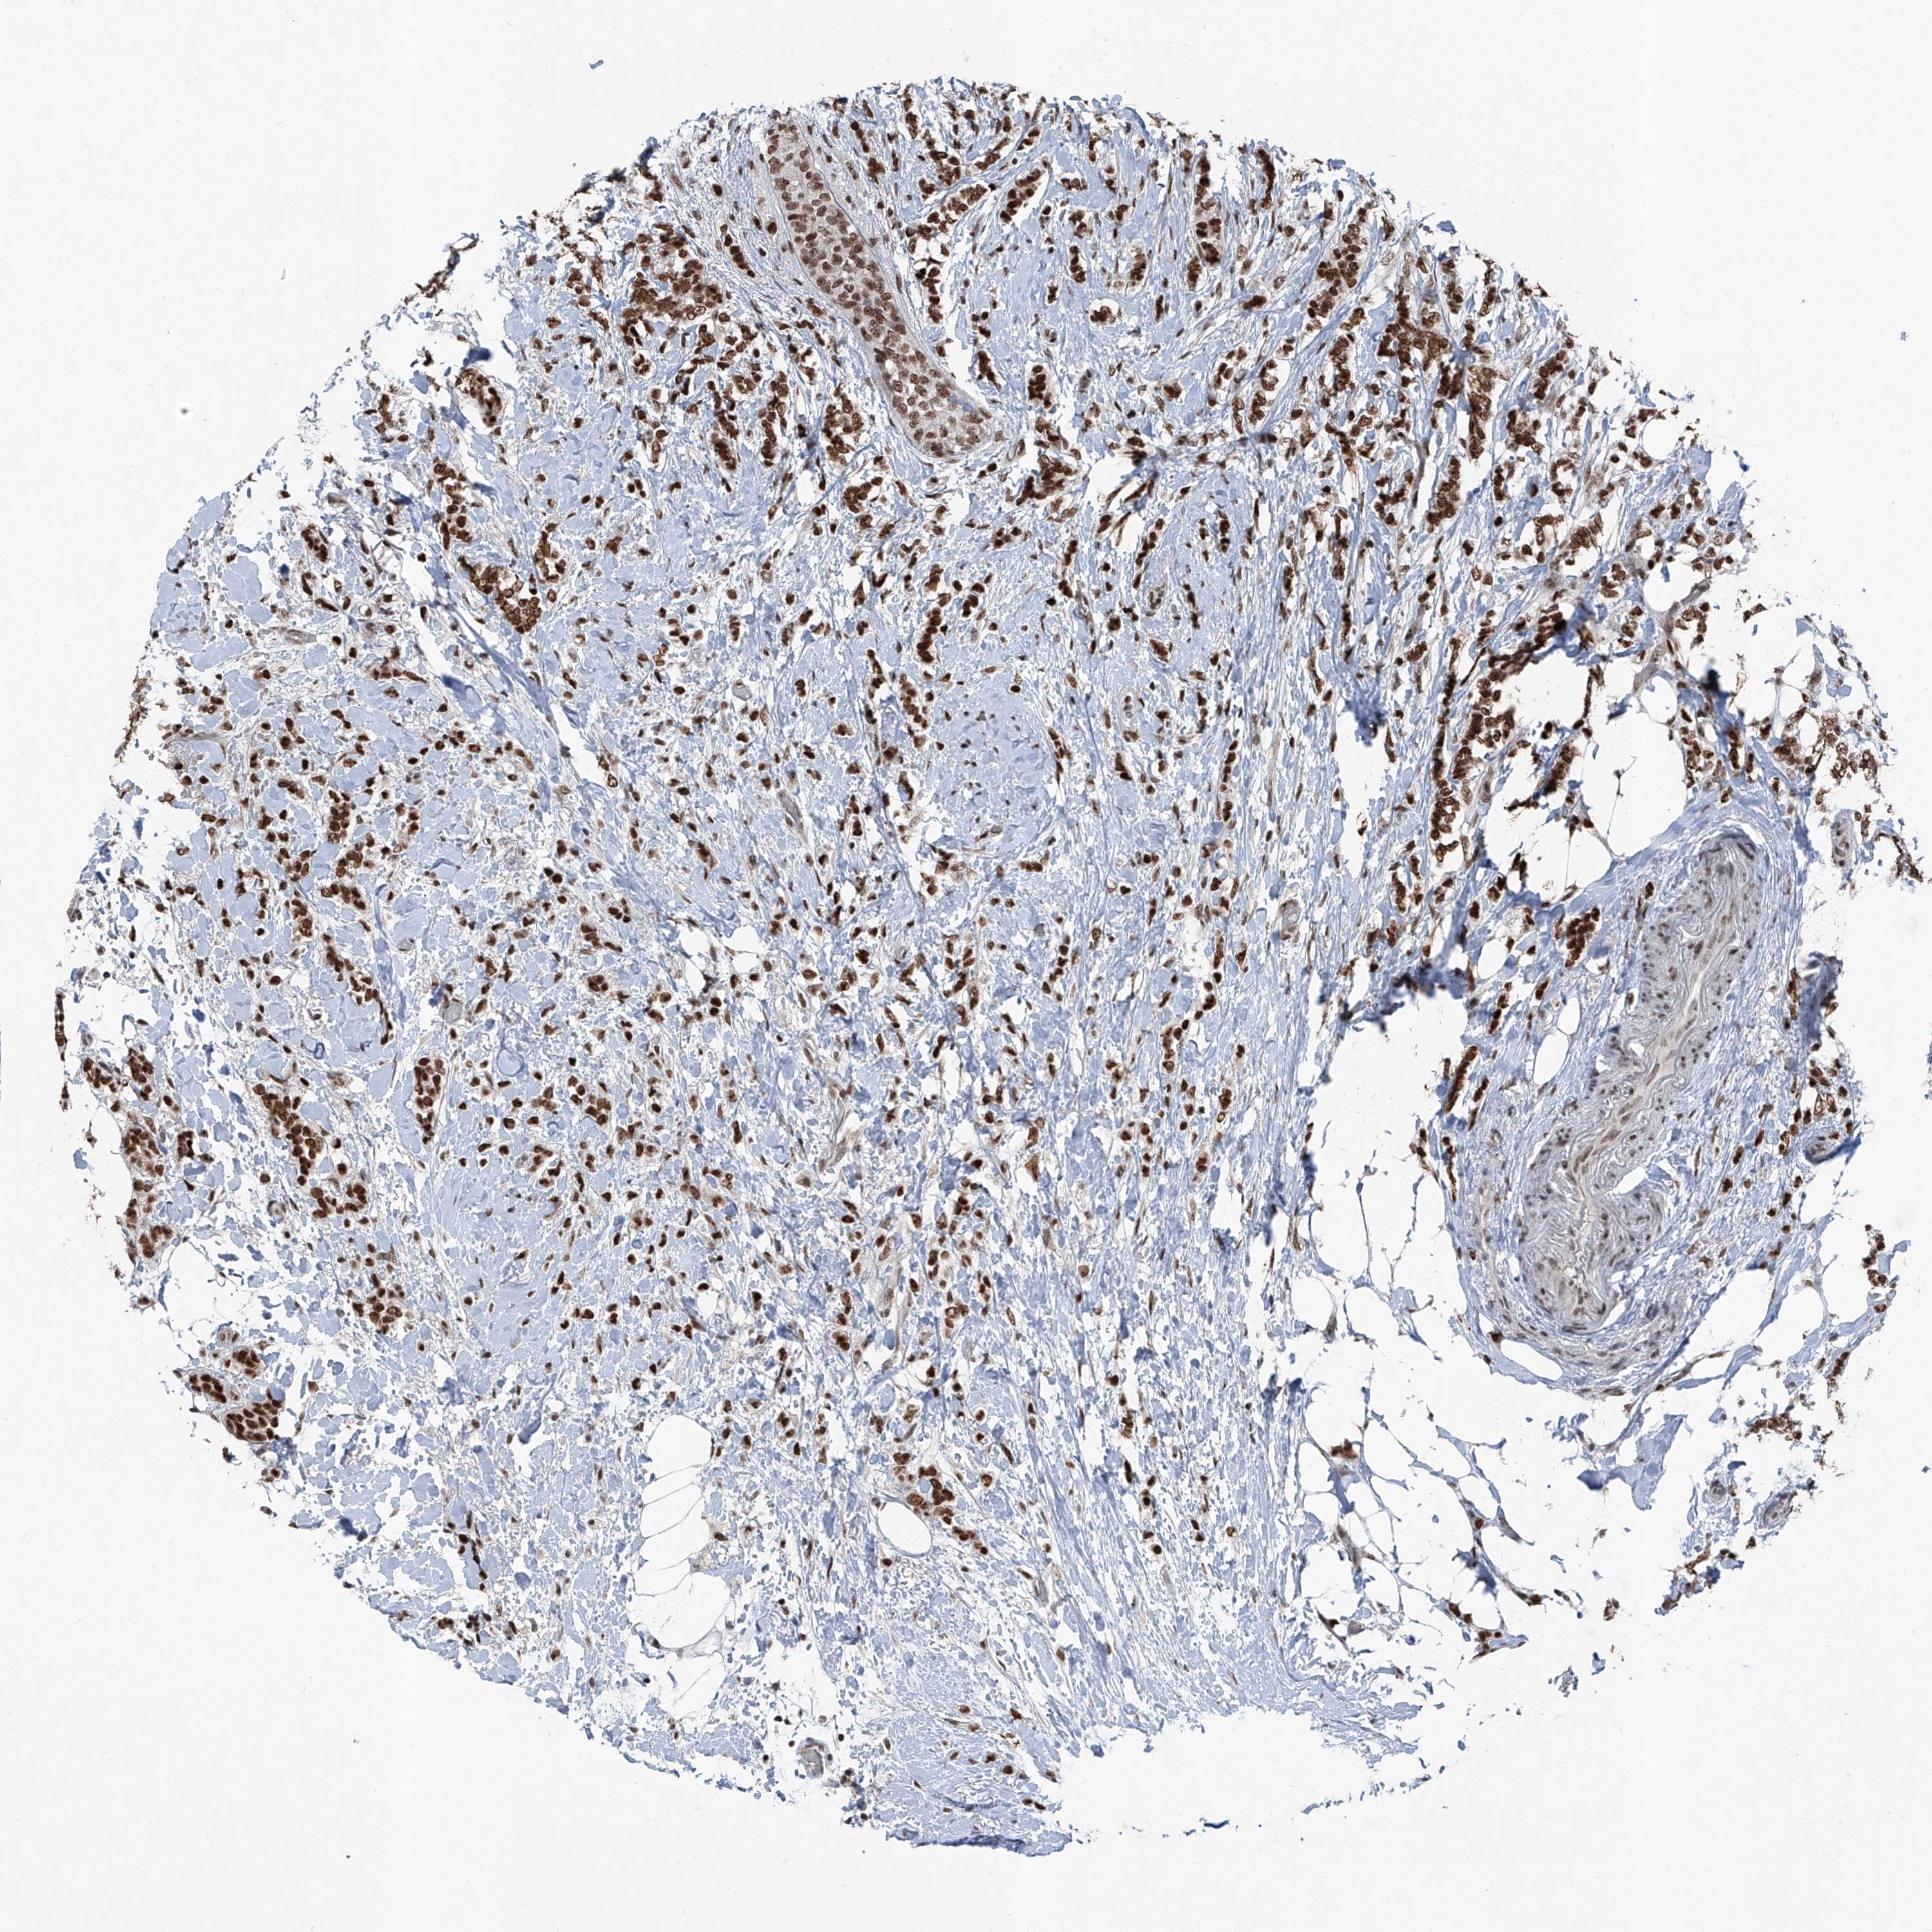

BRCA TCGA BRCA VALIDATION PROTEIN EXPRESSION

ANTIBODIES

AND

VALIDATION